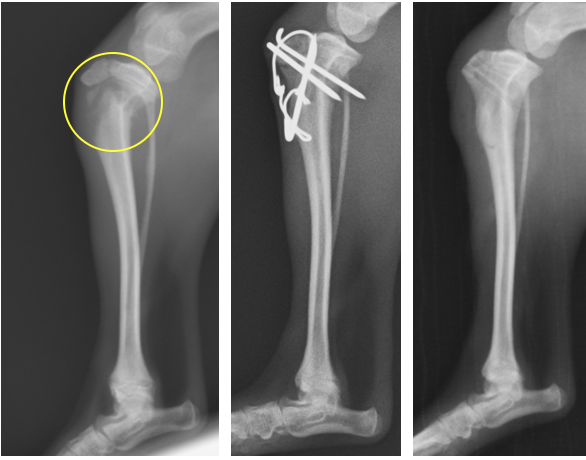

脛骨には成長期の成長板骨折が多く生じます。特に、大腿四頭筋が付着する膝蓋靭帯の付着部である、脛骨粗面が剥離骨折することが多いです。 骨幹部の方では捻じれの力が加わるため螺旋状の骨折が多くなります。特に遠位部分に関しては軟部組織(筋肉や脂肪など)が少ないため、開放骨折(複雑骨折)になってしまうことも少なくありません。

脛骨粗面から、成長版の一帯が骨折してしまっています。脛骨近位は自然と尾側へ偏位してしまうため、ピンとテンションバンドワイヤーによってそれを固定しています。

脛骨粗面のみの骨折です。ここも膝蓋靭帯が近位に引っ張る力が常にかかるため、ピンとテンションバンドワイヤーによって固定しています。